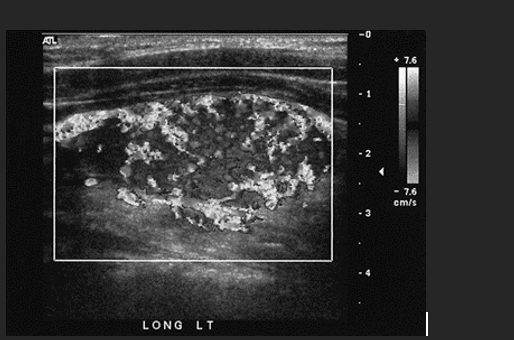

A 35 year old patient presents with a palpable scrotal mall. He is afebrile and denies any scrotal pain. This is most suspicious for what abnormality?

B. Testicular Torsion